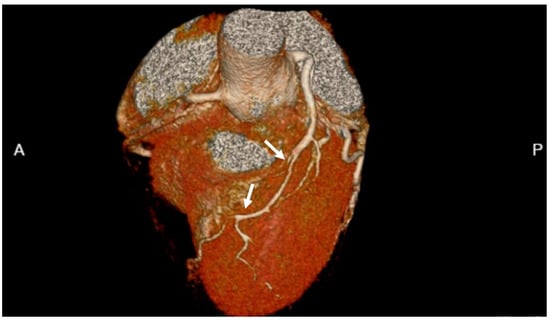

- Tweet, M.S.; Akhtar, N.J.; Hayes, S.N.; Best, P.J.; Gulati, R.; Araoz, P.A. Spontaneous coronary artery dissection: Acute findings on coronary computed tomography angiography. Eur. Heart J. Acute Cardiovasc. Care 2019, 8, 467–475. [Google Scholar] [CrossRef]

- Tweet, M.S.; Gulati, R.; Williamson, E.E.; Vrtiska, T.J.; Hayes, S.N. Multimodality Imaging for Spontaneous Coronary Artery Dissection in Women. JACC Cardiovasc. Imaging 2016, 9, 436–450. [Google Scholar] [CrossRef]